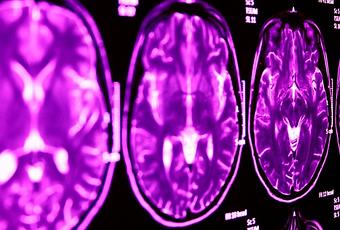

Une découverte clé : à l'aide de l'imagerie cérébrale, les neuroscientifiques montrent que la suppression du gène impacté par la suppression 2p16.3 (Neurexin1) a un impact sur la fonction des zones du cerveau impliquées dans les 2 conditions. Cette suppression génétique perturbe une zone cérébrale connue sous le nom de thalamus, et compromet sa communication avec d'autres zones cérébrales.

Ainsi, la capacité du Thalamus à communiquer avec d'autres zones est altérée par la suppression génétique.